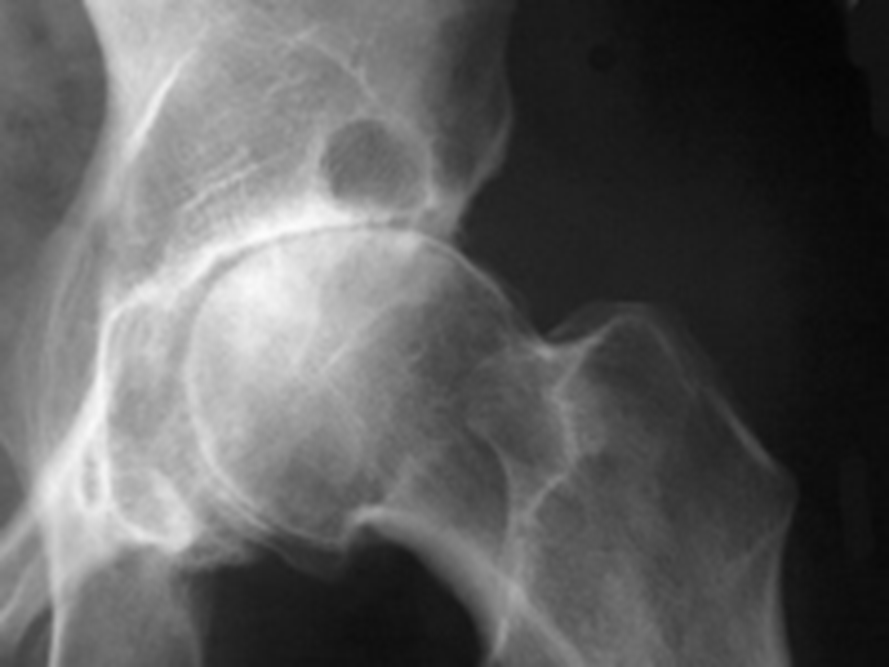

Osteoarthritis

(Degenerative Joint Disease)

Generalized disorder pathologically characterized by loss of joint cartilage and reactive new bone formation.

Cause: traumatic, stress to joints

Complications: joint pain, stiffness, trouble using joints for walking, grasping, etc

Radiographic Appearance: irregular narrowing of joint spaces and development of small bony spurs (osteophytes)

•Knee – articular ends become increasingly dense and joint narrowing is asymmetric

•Fingers – affect distal joints, marginal spurs produce well defined bony protuberances (can palpate and see knobby appearance)

•Hip – asymmetric narrowing of joint space (superiorly and laterally)

Technical: Advance Stage – Subtractive disease

•May require slight decrease

Prognosis: Some patients are unaffected by osteoarthritis while others can be severely disabled.

•Joint replacement surgery for some results in the best long-term outcome.